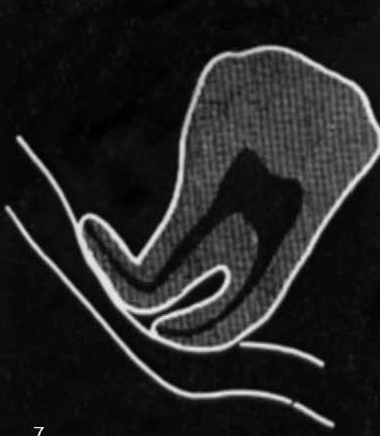

what is this?

Diversion/deflection of the inferior dental canal